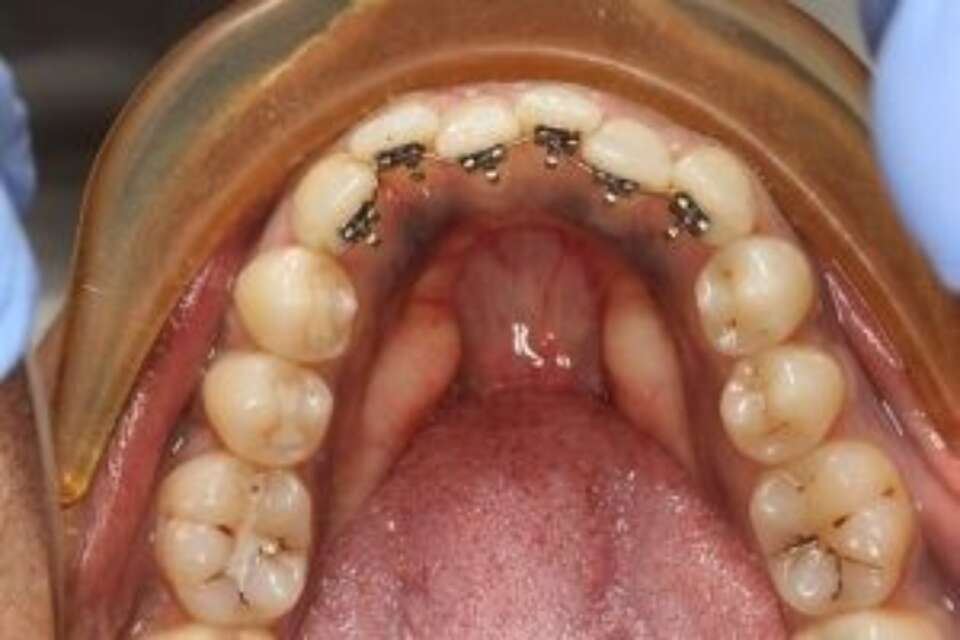

If you would like to see the brackets in action, here is a photo:

social six teeth 2 d brackets

With 2-D brackets - the lowest profile brackets on the market